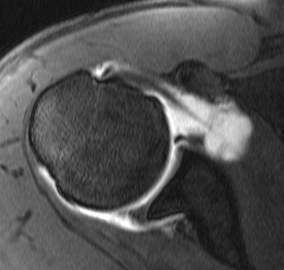

MRI

Supralabral ganglion cyst

- associated with posterior SLAP tears

- www.boneschool.com/suprascapular-nerve-compression